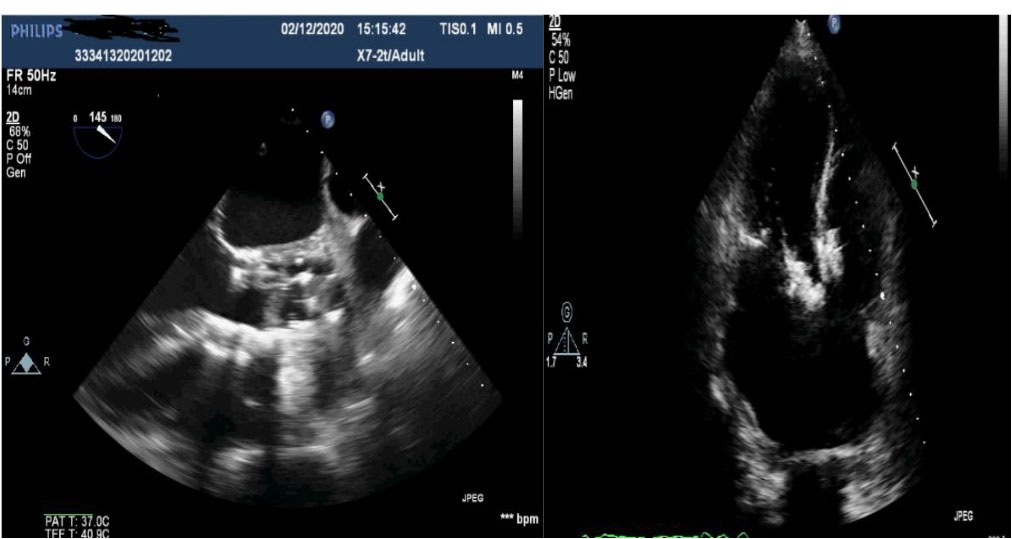

Figure 2.

Ventricular septal defect image after TAVI in transesophageal echocardiography.

Figure 5.

Transesophageal and transthoracic images of the VSD muscular device after the closure of the ventricular septal defect.

The patient was an active 82-year-old woman (NYHA IV) with shortness of breath at rest. Her comorbidities included hypertension and asthma history. During her examination, she was found to have normal left ventricular (LV) systolic function (ejection fraction; 60%) and severe calcific aortic valve stenosis (aortic valve area: 0.7 cm2; peak / mean gradient: 85/55 mm Hg) on transthoracic echocardiography (TTE). Coronary angiography was found to have normal coronary vessels. The patient with 5.1% STS score was decided to undergo TAVI by our Heart Team. On multi-slice cardiac computed tomography (CT), severe calcification from the aortic valve level and calcified nodule towards the LVOT were noted. Calcific nodule extending to LVOT shown in . The procedure was briefly performed as follows: A 6-F sheath was placed in the right common femoral artery and vein then proglide was inserted. A stiff wire was then inserted through a pig tail catheter. 19 F delivery catheter has been advanced from descending aorta. By performing fast pacing, a nucleus 20×40 mm balloon was predilated and a self-expandable 29 mm Portico prosthesis was implanted. At this stage, there was second grade aortic ınsufficiency (AR) and the prosthesis was postdilated with nucleus 25×40 mm balloon. After the procedure, a very good result was obtained with only minimal insufficiency and elimination of the aortic gradient. No problem developed during the follow-up during hospitalization and no obvious pathology was detected in the post-procedure follow-up echocardiography. However, a pansystolic murmur was detected in the physical examination of the patient with dyspnea at the follow-up 1 month later, and aortic Portico prosthesis (maximum gradient:11 mm Hg, minimal insufficiency) was detected on TTE. However, the right chambers were dilated with significant tricuspid regurgitation and an increased systolic pulmonary artery pressure of 60 mm Hg. In addition, a perimembranous VSD 7 mm was evident beginning from the edge of the prostetic valve, resulting in a significant left-to-right shunt. Based on these findings , it was decided to perform interventional treatment of the defect using the Amplatzer muscular VSD occluder. Right femoral artery and vein canulated using 6-F sheath. A pigtail catheter was passed to the LV. A 0.035 hydrophilic wire and 5-F JR-3.5 catheter were then passed through the VSD to the RV. The wire unintentionally went into the inferior vena cava and the catheter sent over the wire to the inferior vena cava. Then the hidrofilic wire was exchanged with a 0.035 300 cm Noodle wire. The wire was snared in the inferior vena cava and externalized through the right femoral vein. From the right femoral vein a 7-f delivery sheath sent to the ascending aorta through inferior vena cava and the VSD. VSD diameter was measured 7 mm by ventriculography and 8 mm with TOE. Later, 10 mm Amplatzer muscular VSD occluder device was sent through the long sheath, and the first disc was opened in the ascending aorta. Then the system was pulled back to the VSD and the second disc was unsheated (). On 3D-TOE the occluder device was in a correct position, and there was a minimal shunt possibly through the occluder device (). It was disconnected from the delivery cable after confirming that there was no compression or problem with the aortic valve. Two days after the procedure, the device was in a good position, there was mild tricuspid regurgitation and systolic pulmonary artery pressure was 40 mmHg (). After one week of follow-up, the patient was discharged home. It continues to be active with significant improvement in shortness of breath (NYHA I-II) twelve months after the procedure.